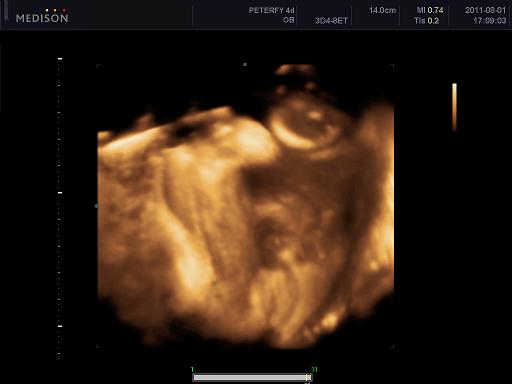

Velünk minden oké szerencsére, dundisodok én is, a baba is tök szuperül van ééééés tegnap voltunk végre 4D-n, annyira nagy élmény volt lányok!!!! Nem is gondoltam h ez ennyire jó dolgo, azzal együtt, hogy Alma nagyon bújócskázott, végig az arcát simizte meg takargatta, csak néha kaptunk egy kis mosolyt de imádom, végtelenül nagy boldogság ez a kis csöppség!!!!! :)

1250 grammos és kis ficánka, meg a szonográfus csaj is mondta hogy mennyire kis cserfes már most! :D

Kép